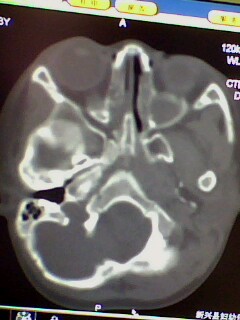

腺样体肥大,双侧上颌窦炎症,原因支持楼主。乳突体位不正,个人发育有差异,观察吧。

腺样体肥大,右侧扁桃体炎,双侧上颌窦炎症(鼻窦炎)

腺样体肥大,副鼻窦炎症

腺样体肥大,鼻窦炎。

腺样体肥大,副鼻窦炎症。支持!乳突尚未发育完全,加上位置不标准不好说。